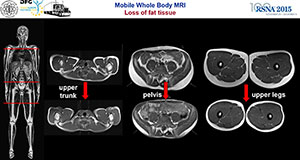

CHICAGO — Using a mobile MRI truck, researchers followed runners for 4,500 kilometers through Europe to study the physical limits and adaptation of athletes over a 64-day period, according to a study presented today at the annual meeting of the Radiological Society of North America (RSNA).

The Trans Europe Foot Race (TEFR) took place from April 19 to June 21, 2009. It entailed running 4,487 km starting in southern Italy and ending in the North Cape in Norway without any day of rest. Forty-four of the runners (66 percent) agreed to participate in the study.

The research team's most important tool was a 1.5 Tesla MRI scanner mounted on a mobile unit, the only one of its kind in Europe at that time. Each participant was scanned every three to four days, resulting in 15 to 17 MRI exams over the course of the race. The runners were also randomly assigned to additional examinations, and protocols were created for daily urine, blood and other tests.